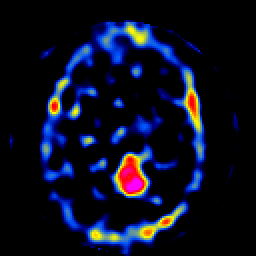

SPECT TL Study #8 -- Slice #31